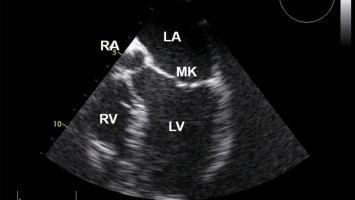

Howto FoCUS: Tipps zum fokussierten Herzultraschall im Notfall

Die fokussierte Sonographie des Herzens (FoCUS) ist integraler Teil der Notfallsonographie. Welche klinischen Fragestellungen können mittels FoCUS beantwortet werden? Welche Schallfenster und Schnittebenen sind relevant? Dieser Beitrag vermittelt die Grundlagen und beschreibt fünf typische Befundkonstellationen bei Schock.

Konsensuspapier zur fokussierten transösophagealen Echokardiographie (fTEE) in der Klinischen Akut- und Notfallmedizin

Die fokussierte transösophageale Echokardiographie (fTEE) wird neben der Intensivmedizin zunehmend auch in Notaufnahmen angewandt. Eine fTEE sollte nur im Rahmen der erweiterten kardiopulmonalen Reanimation oder im unklaren Schockgeschehen …

Neue Empfehlungen: fokussierte transösophageale Echokardiographie in Akut- und Notfallmedizin

Voraussetzungen, Indikationen und Praxistipps: Ein neues Konsensuspapier gibt umfassende Empfehlungen zum Einsatz der fokussierten transösophagealen Echokardiographie (fTEE) in der klinischen Akut- und Notfallmedizin. Verfasst von der Kommission für Klinische Kardiovaskuläre Medizin der DGK in Kooperation mit der DGINA, DGIIN und DGIM.

Digitales Blutdruckmessgerät/© Kotchakorn / Stock.adobe.com (Symbolbild mit Fotomodell), Injektionsnadeln für Regionalanästhesie/© zlikovec / Getty Images / iStock, Reanimation/© Rea / stock.adobe.com, Langzeit-EKG mit junktionalem Ersatzrhythmus/© O. Schäfer, Fokussierter Herzultraschall (FoCUS)/© Dieter von Ow / all rights reserved Springer Medizin Verlag GmbH, Pulsoximeter wird an Finger angeschlossen/© Yakobchuk Olena / stock.adobe.com, Rhabdomyom im Kindesalter /© Höck M et al. doi.org/10.1007/s00112-025-02259-w unter CC-BY 4.0, Eine Pinzette wird vom Tisch genommen während einer OP/© JazzIRT / Getty Images / iStock (Symbolbild mit Fotomodellen), Venöse CT-Angiografie: Sinusthrombose/© Wohlfahrt L. et al. / all rights reserved Springer Medizin Verlag GmbH, Übergabesituation im Herzkatheterlabor/© Ernst M et al. / all rights reserved Springer Medizin Verlag GmbH (Symbolbild mit Fotomodellen), Frau misst Blutdruck/© Microgen / stock.adobe.com (Symbolbild mit Fotomodell), Transösophageale Echokardiographie (fTEE), 4‑Kammer-Blick/© Michels M et al. / all rights reserved Springer Medizin Verlag GmbH, Screening auf Präeklampsie/© Musik T et al. / all rights reserved Springer Medizin Verlag GmbH, Arzt nimmt Schwangeren Blut ab/© Andrey Popov / stock.adobe.com (Symbolbild mit Fotomodellen), Patient im Gespräch mit Ärztin/© sebra / stock.adobe.com (Symbolbild mit Fotomodellen), Mann hält Tablette und ein Glas Wasser in den Händen/© somenski / Fotolia (Symbolbild mit Fotomodell), Herpes Zoster am Rücken/© Mumemories / Getty Images / iStock (Symbolbild mit Fotomodell), EKG befunden mit System - EKG Essential/© Springer Medizin Verlag GmbH